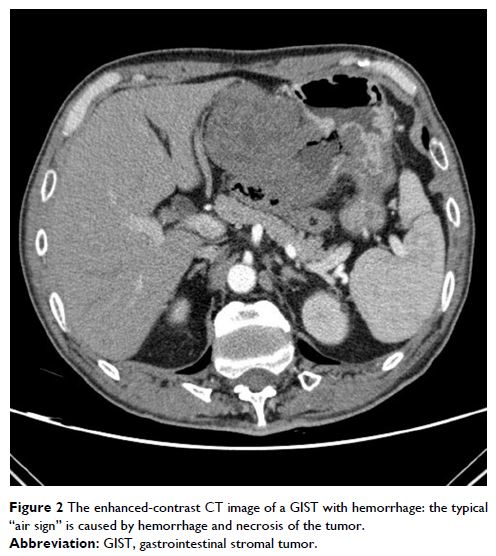

Review

- 作者:Qi Liu, Fanmin Kong, Jianping Zhou, Ming Dong, Qi Dong

- 期刊:Cancer Management and Research